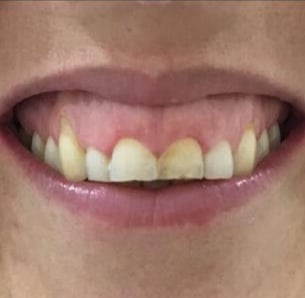

NUESTROS CASOS REALES